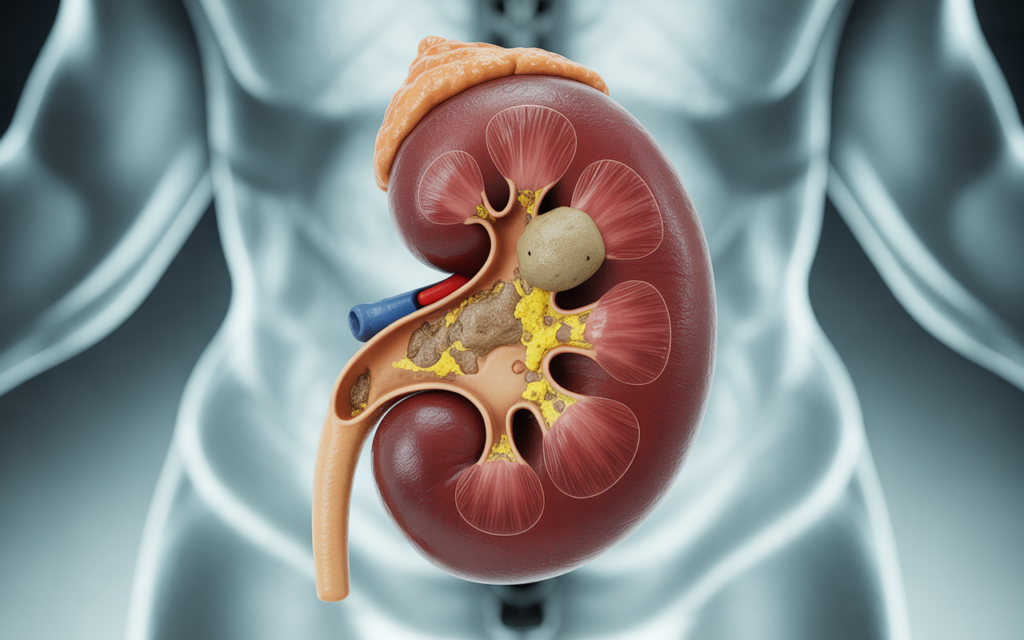

Diagnosis and Medical Evaluation

Doctors use imaging tools such as CT scans, ultrasounds, and X-rays to locate stones. Blood and urine tests provide insights into mineral levels and underlying causes.

Tests may reveal:

- High calcium or oxalate.

- Low citrate levels in urine.

- Signs of infection or inflammation.

Medical professionals often combine diagnostics with nephrologist advice on kidney stones to recommend treatment or preventive strategies.

Medical Treatment for Kidney Stones

When stones cannot pass naturally, medical intervention is required.

- Shock wave therapy for kidney stones uses sound waves to break stones into smaller pieces.

- Ureteroscopy for kidney stones involves inserting a scope to remove or fragment stones.

- Medications help with uric acid stone dissolution and calcium oxalate stone treatment.

These minimally invasive kidney stone treatments are effective and safe, reducing hospital stays and recovery time.